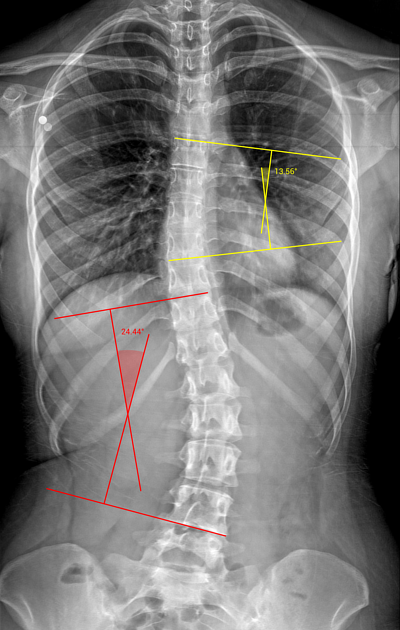

Detects key anatomical landmarks and analyzes pediatric spinal X-rays to assist in measuring curvature angles and deformities.

Generates measurements in ~3 seconds, significantly reducing the time required for manual analysis.

Achieves >90% reproducibility comparable to consultant measurements, while being EHR-agnostic and easy to integrate into clinical workflows.